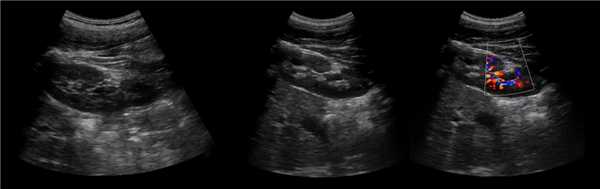

Клинический пример из первой группы. Пациент М., с хронической почечной недостаточностью. Трансплантация почки произведена от живого родственного донора. Трансплантат находится в правой подвздошной области. При нормальном функциональном состоянии трансплантата, показатели цветовой и спектральной допплерографии оценивались как удовлетворительные, с индексом резистентности не более 0,60 (рис. 1); показатели жесткости паренхимы почечного трансплантата при УЭСВ на различных участках составили от 20,05 до 29,18 кПа (рис. 2-4).

Рисунок 1. Ультразвуковое исследование в режиме цветовой и спектральной допплерографии в междольковых и сегментарных артериях у пациента М. Показатели кровотока в данном случае не изменены

У пациентов второй группы, при нормальных показателях клинико-лабораторных и допплерографических исследований, показатели жесткости почечного трансплантата составили 17,00-26,06 кПа.